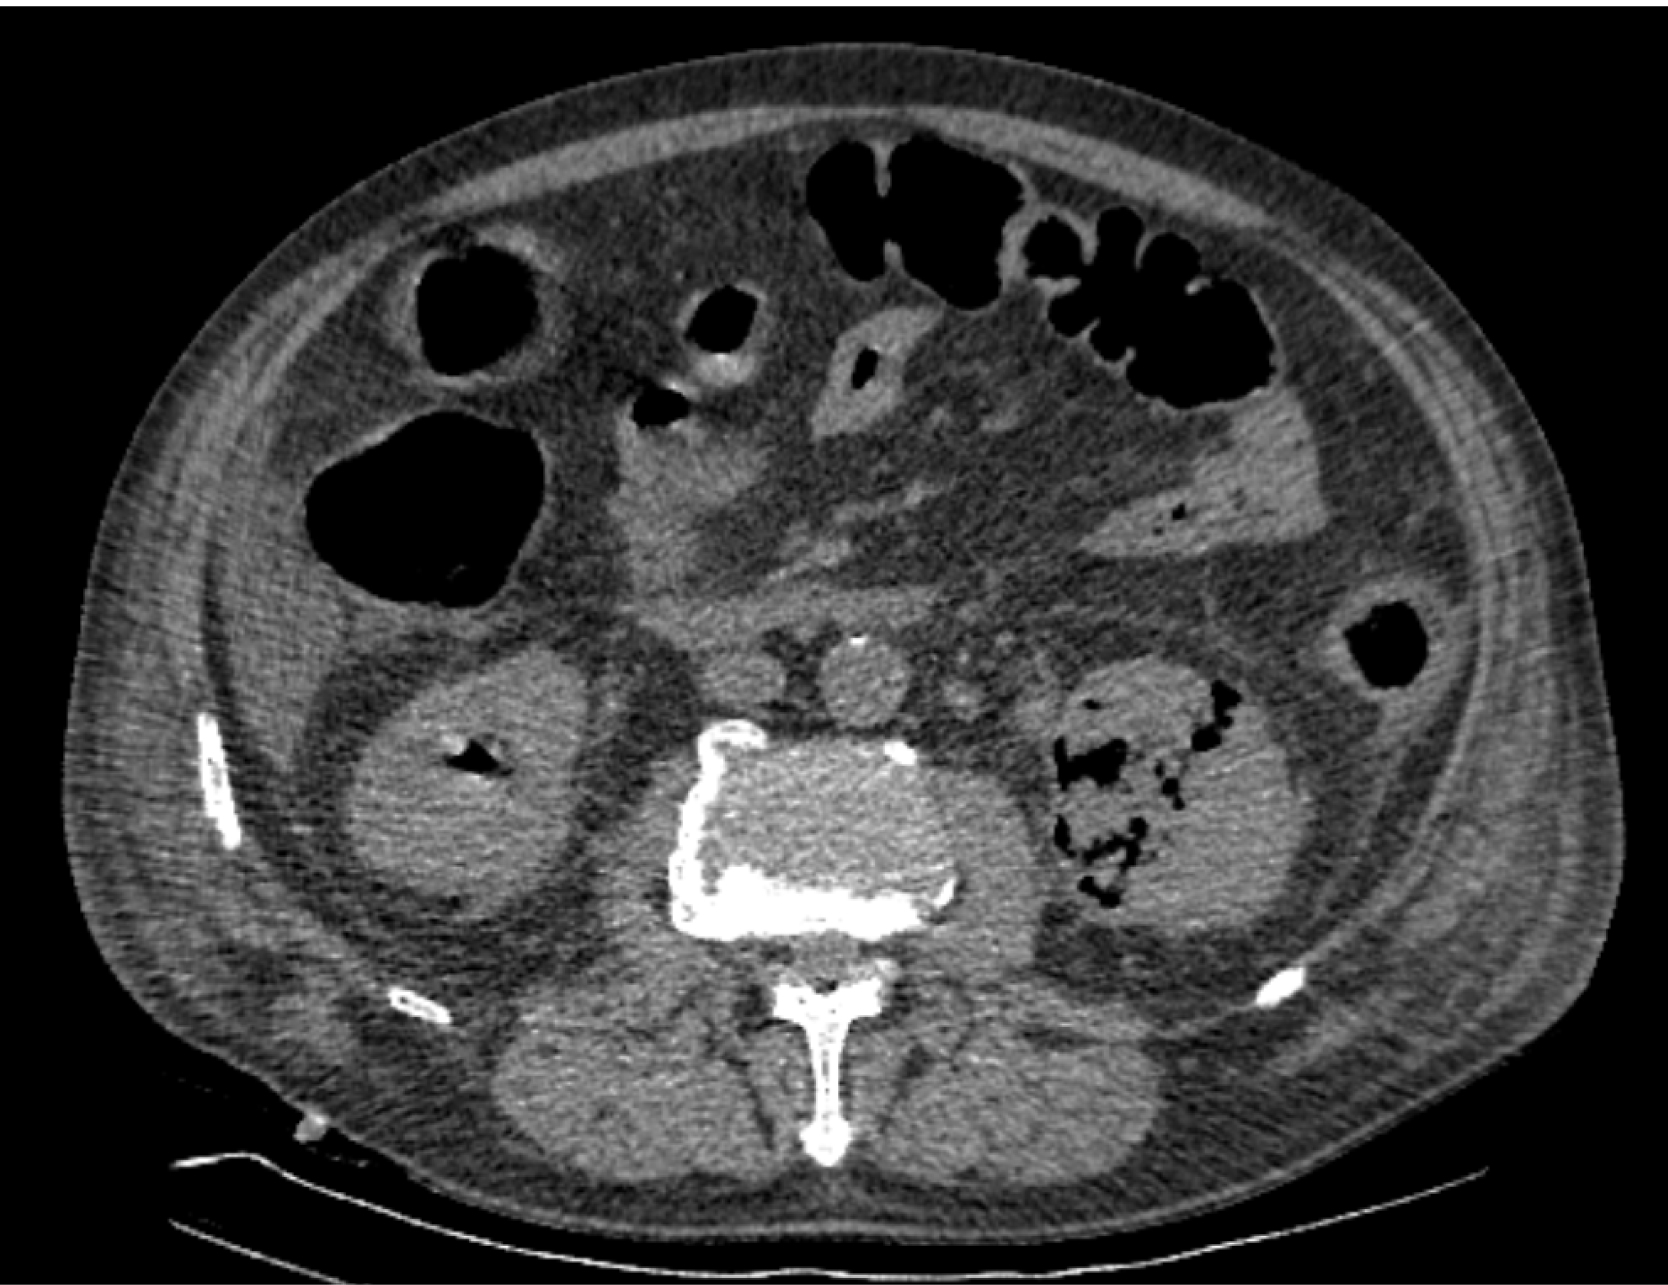

На следующий день состояние пациента оставалось тяжелым, с отрицательной динамикой, креатинин сыворотки возрос до 735,2 ммоль/л, Появились жалобы на слабость, тошноту. При осмотре: живот мягкий, вздут по всем отделам, при пальпации болезненный. Область почек не изменена, при пальпации безболезненна, патологических изменений в области почек не выявлено. Симптом поколачивания отрицательный билатерально. При УЗИ были обнаружены плевральный выпот по 300–400 мл с каждой стороны, гепатомегалия, увеличение размеров селезенки, асцит. Кроме того, в обеих почках были визуализированы тени, характерные для конкрементов. По данным компьютерной томографии (КТ) конкрементов не обнаружено, но в лоханке, на всем протяжении левого мочеточника и, частично, в правом мочеточнике, а также в мочевом пузыре визуализировался газ (рис. 1–6).

Рис. 4. Компьютерная томография органов брюшной полости, забрюшинного пространства, органов малого таза. Газ в почках

Рис. 5. Компьютерная томография органов брюшной полости, забрюшинного пространства, органов малого таза. Газ в левой почке

Рис. 6. Компьютерная томография органов брюшной полости, забрюшинного пространства, органов малого таза. Газ в верхнем полюсе левой почки